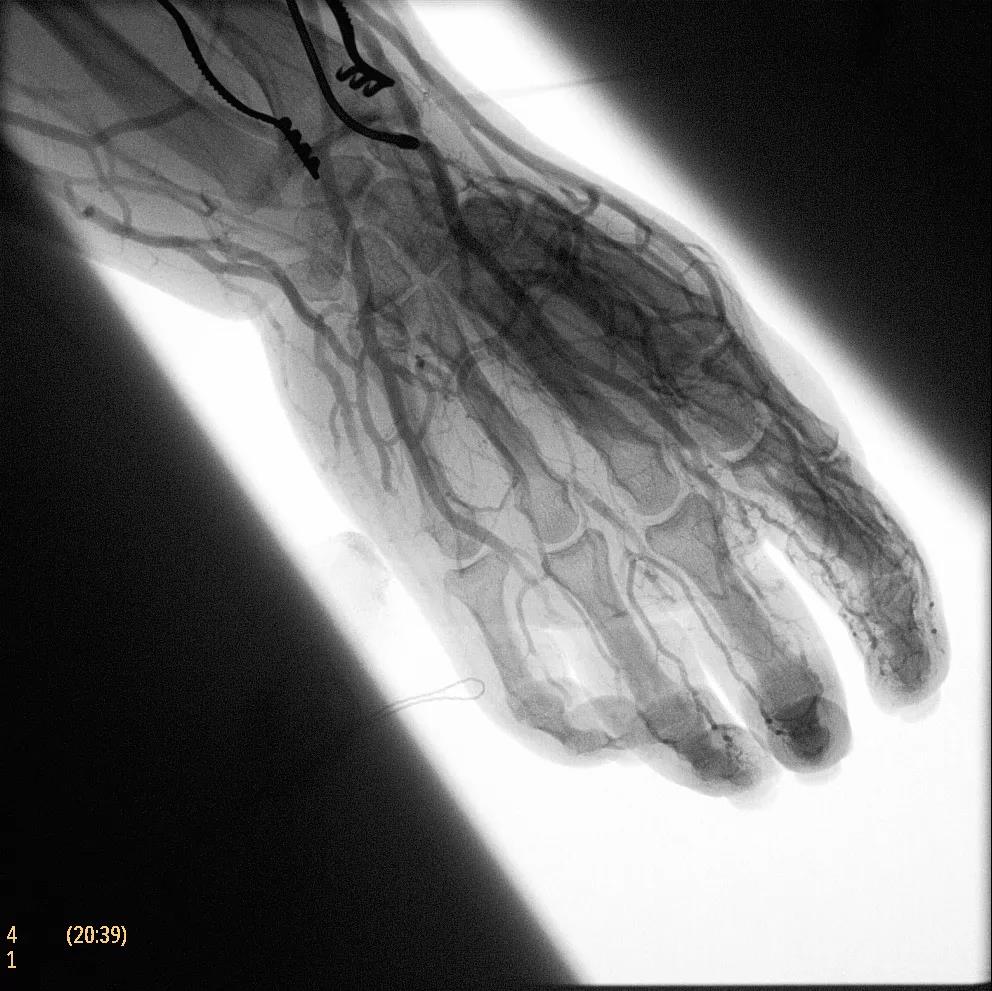

為了獲得清晰的高質量圖像,Zenition 70 采用了與公司Azurion平臺相同的圖像處理算法,可提供患者解剖結構的高清可視化和更大的可視區(qū)域。飛利浦的MetalSmart軟件等功能可確保圖像質量,該軟件可自動調整圖像的對比度和亮度,以便在視野中存在金屬物體(如植入物)時提高圖像質量 - 這一特性使Zenition 70在整形外科中特別有用。